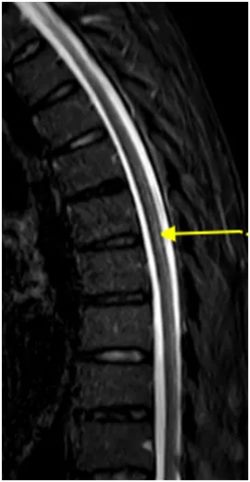

半年前,王先生开始感觉走路不稳,像踩在棉花上,还伴有肢体麻木无力。这些症状逐渐加重,最终他来到郑州大学第五附属医院神经内科二病区就诊。检查发现,他患有巨幼红细胞性贫血,维生素B12水平明显偏低。脊髓磁共振结果显示:胸段脊髓后索出现异常高信号(如图黄色箭头所示),轴位图上更是呈现出典型的倒“V”征(绿色箭头)。